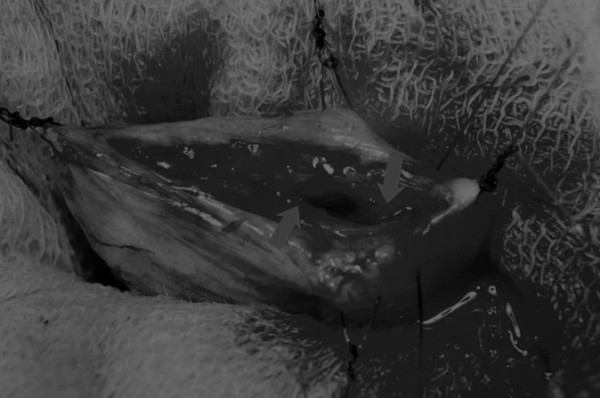

图5 通过导尿管注入无菌生理盐水反向冲洗,可以去除微小的结石(箭头)和夹杂在膀胱黏膜皱褶中的砂样结石,以及可能在手术中形成的血块